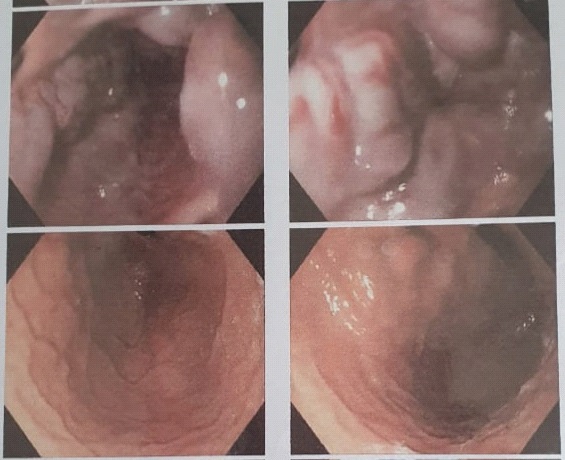

A vascular doppler sonography showed decreased portal venous velocity which indicate portal hypertension. Magnetic resonance cholangiopancreatography (MRCP) disclosed multifocal cystic dilatation of intrahepatic bile ducts, the common bile duct was undetectable appearance suggestive of liver cirrhosis, and splenomegaly (Figure 2).

Figure 2: MRCP.

MRCP: disclosed multifocal cystic dilatation of intrahepatic bile ducts